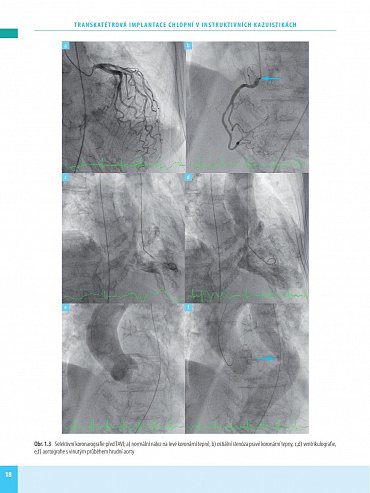

Transkatétrová implantace chlopní (TVI) je minimálně invazivní výkon umožňující náhradu poškozené srdeční chlopně - aortální nebo mitrální. Preferuje se zejména u pacientů s vysokým rizikem komplikací chirurgického výkonu na otevřeném srdci. Kniha obsahuje velký počet pečlivě vybraných kazuistik se stručným schématem diagnostického postupu, diferenciální diagnostikou a technikou operace. Vlastní popis je doplněn množstvím zobrazovacích vyšetření a peroperačních fotografií, které umožní orientaci čtenáře a pochopení základních kroků diagnostiky a léčby.